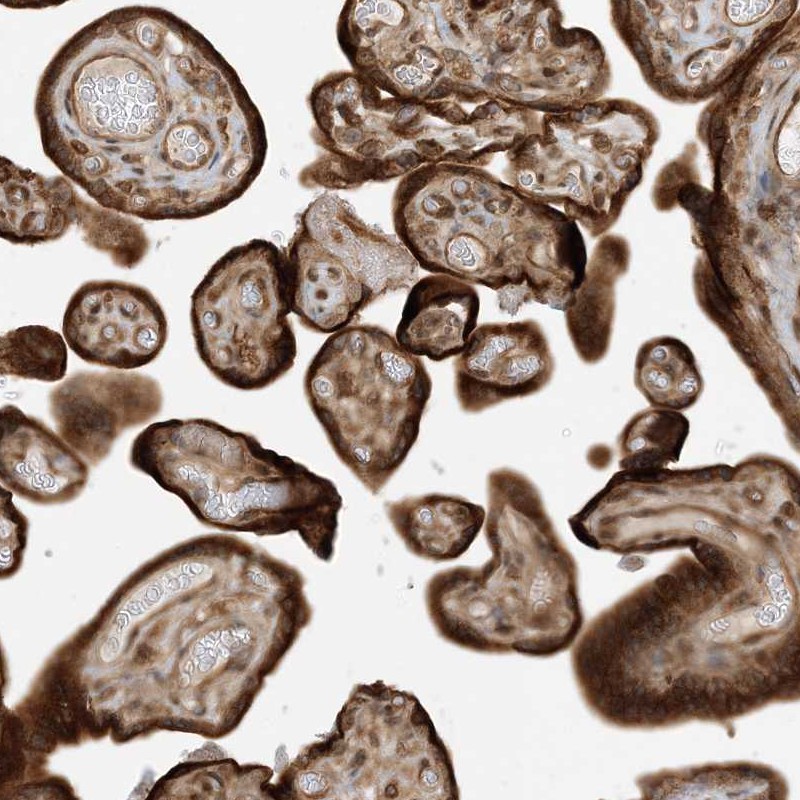

Immunohistochemical staining of human placenta shows strong cytoplasmic positivity in trophoblastic cells.